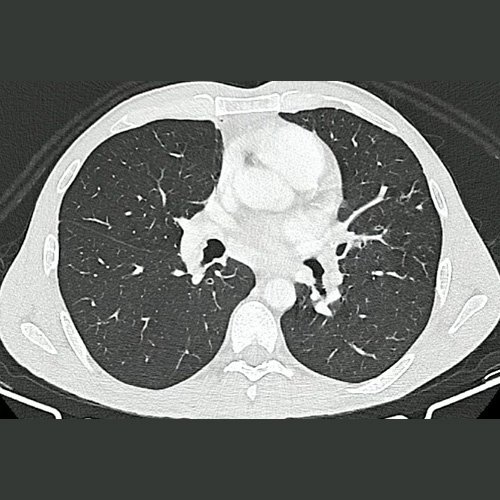

• TAC de tórax con contraste EV (DÍA 1): Persiste adenopatía mediastinal subcarinal de 16 mm de diámetro en su eje corto. El resto de los ganglios mediastinales visibles son de tamaño y morfología normal. El árbol traqueobronquial no presenta alteraciones. El análisis del parénquima pulmonar muestra múltiples pequeñas bronquiectasias de paredes gruesas, asociadas a discreto patrón de árbol en brote y a pequeñas atelectasias laminares subsegmentarias, en segmento anterior del lóbulo superior derecho, lóbulo medio, segmentos lingulares, y segmentos basales de ambos lóbulos inferiores. Hallazgos ya presentes en estudio anterior.

Tomografía de tórax (Ventana pulmonar-corte axial) DÍA 1